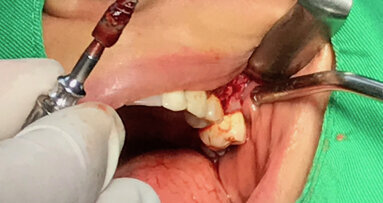

Viditelná granulační tkáň v místě resorpce a fraktury zubu 11.

Po atraumatické extrakci zubu 11 bylo možno díky laseru Fotona LightWalker důkladně očistit lůžko zubu od zánětlivé tkáně vzniklé vlivem chronického zánětlivého stavu. Dále byla provedena dezinfekce lůžka zubu laserem Nd:YAG. Implantát byl zaveden ve správné, předem naplánované, pozici s použitím chirurgické šablony vytištěné v Belgii ze speciální lékařské pryskyřice (s možností sterilizace výrobku před výkonem). Po sejmutí šablony byla našroubována korunka spolu s abutmentem (cementováno předem mimo ústa pacienta) do implantátu a dále byla provedena fotomodelace tkání laserem Nd:YAG s cílem získání lepšího a rychlejšího hojení. Kontrolní CBCT vyšetření ukázalo ideální lokalizaci implantátu vzhledem k plánované pozici.